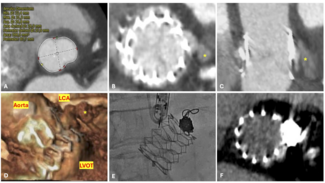

Therapy with 325 mg aspirin, loading 600 mg clopidogrel, and 5.000 IU unfractionated heparin was started, and the patient was immediately transferred to the catheterization laboratory. Coronary angiography showed total occlusion of mid left anterior descending (LAD) coronary artery, with thrombolysis in acute myocardial infarction (TIMI) 0 flow as shown in Figure 2. After vessel  wiring through an Extra Back Up 6 Fr guiding catheter (Medtronic), an aspiration catheter (6 Fr Export AP; Medtronic) was inserted. The blood clot was successfully aspirated with immediate relief of pain and resolution of ST segment elevation. TIMI III flow was restored with no residual lesions at the site of thrombus or the distal parts of the vessel (Figure 3). A decision was made not to deploy a balloon or a stent in the affected area. Left circumflex and right coronary arteries were normal, as detected 1 year before.

wiring through an Extra Back Up 6 Fr guiding catheter (Medtronic), an aspiration catheter (6 Fr Export AP; Medtronic) was inserted. The blood clot was successfully aspirated with immediate relief of pain and resolution of ST segment elevation. TIMI III flow was restored with no residual lesions at the site of thrombus or the distal parts of the vessel (Figure 3). A decision was made not to deploy a balloon or a stent in the affected area. Left circumflex and right coronary arteries were normal, as detected 1 year before.